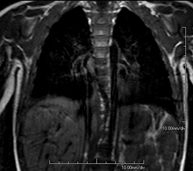

Chest MRI

This non-invasive diagnostic procedure uses an electromagnetic field and radio waves (from a transmitter and receiver) to acquire high-definition anatomical images of the chest. It is a radiation-free procedure. It is indicated for lung lesions in which infiltration of the mediastinum or thoracic wall must be ruled out, to differentiate between solid and cystic chest lesions, etc. Sometimes paramagnetic contrast (gadolinium) must be used to complete the study.